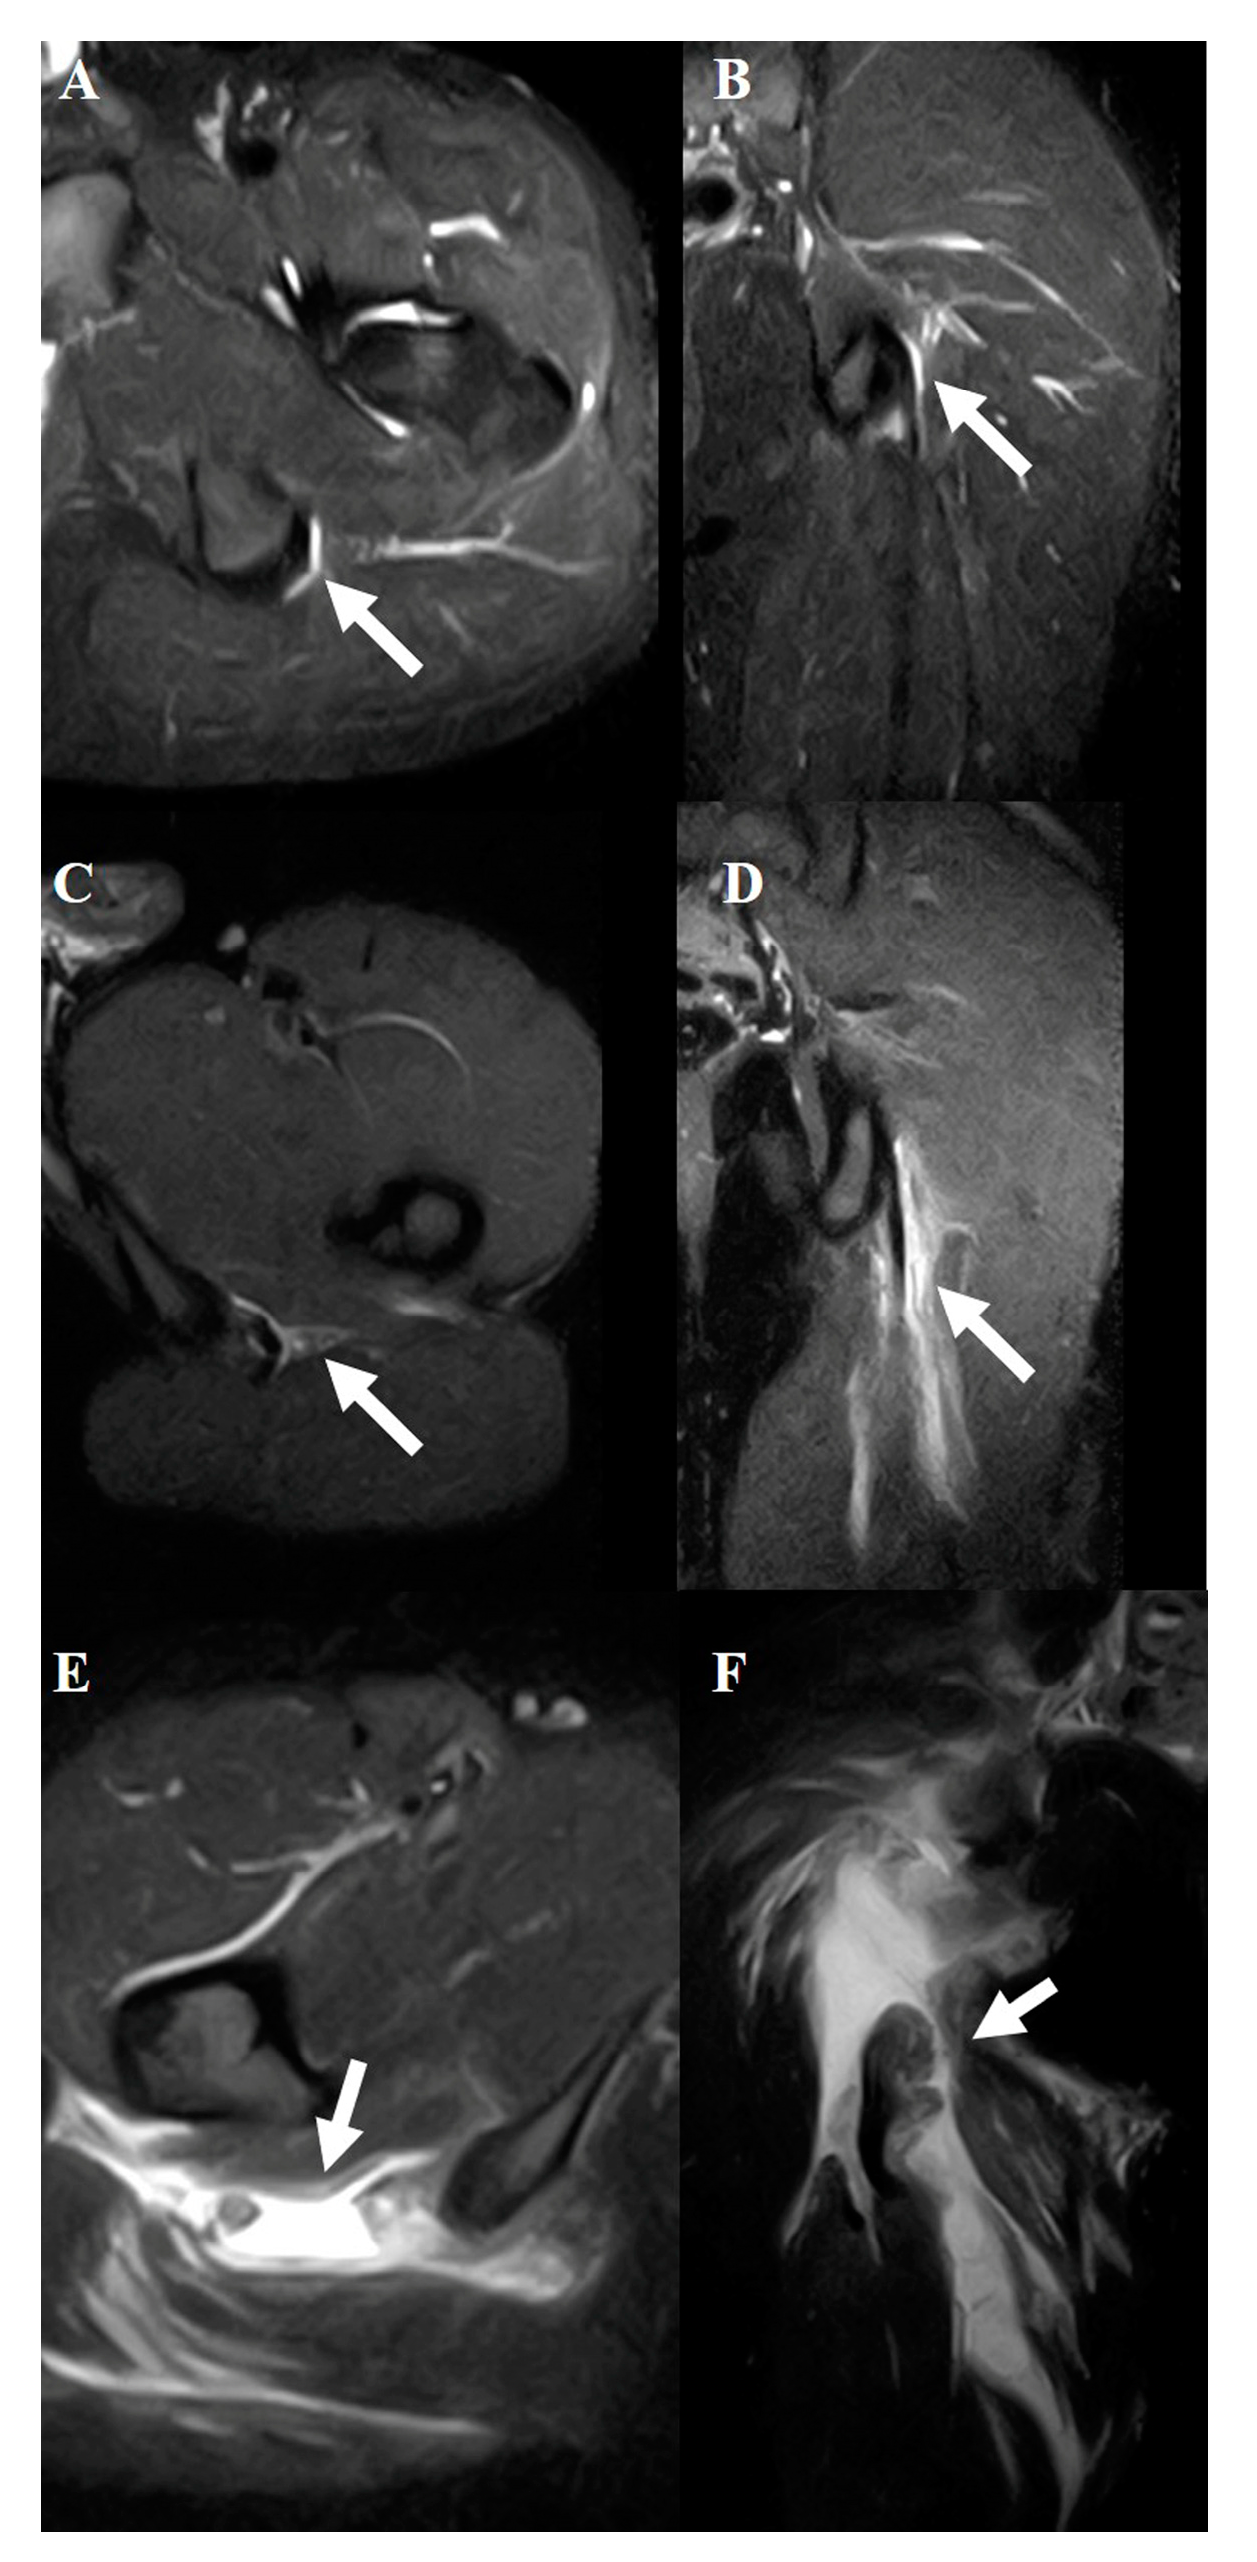

Figure 2. Typical MRI findings in musculotendinous junction injury.Axial (A) and coronal (B) views of grade 1. Axial (C) and coronal (D) views of grade 2. Axial (E) and coronal (F) views of grade 3. The white arrows indicate the injured area.